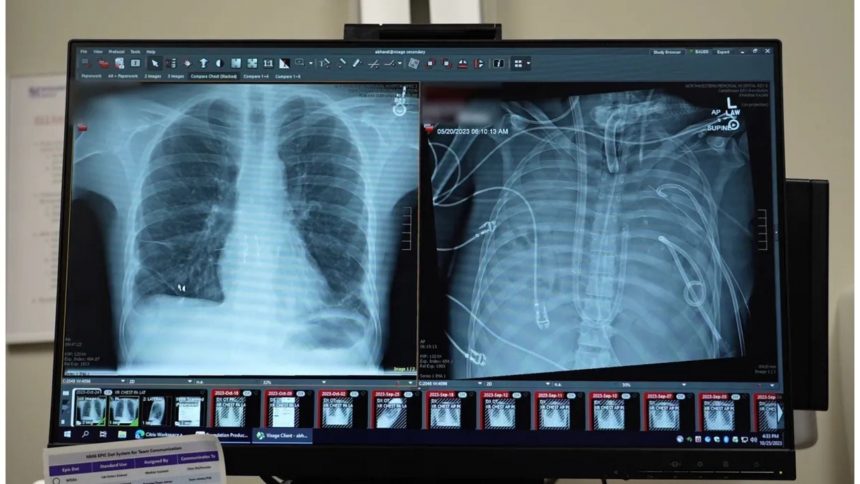

La infección era tan grave que los pulmones quedaron gravemente dañados y el corazón y los riñones también estaban empezando a sufrir las consecuencias. De hecho, poco después del ingreso fue necesario practicarle una RCP por un paro cardíaco. Estaba claro que, para detener la infección, había que extirpar el foco y, con él, los pulmones. Sin embargo, no había órganos compatibles en ese momento. Además, incluso si los hubiera, el cuerpo estaba demasiado dañado por la infección para aceptar nuevos órganos. Los habría rechazado de inmediato. Por todo esto, no quedó más remedio que intentar mantener al paciente sin pulmones hasta paliar la infección y encontrar a un donante. Por suerte, fue un éxito.

Durante los dos días que estuvo sin pulmones, la sangre se mantuvo oxigenada y con un flujo adecuado para garantizar el funcionamiento del sistema inmunitario que, junto a los antibióticos, ayudó a tratar la infección bacteriana. Ya estaba listo para recibir los órganos que llegaron justo a tiempo.